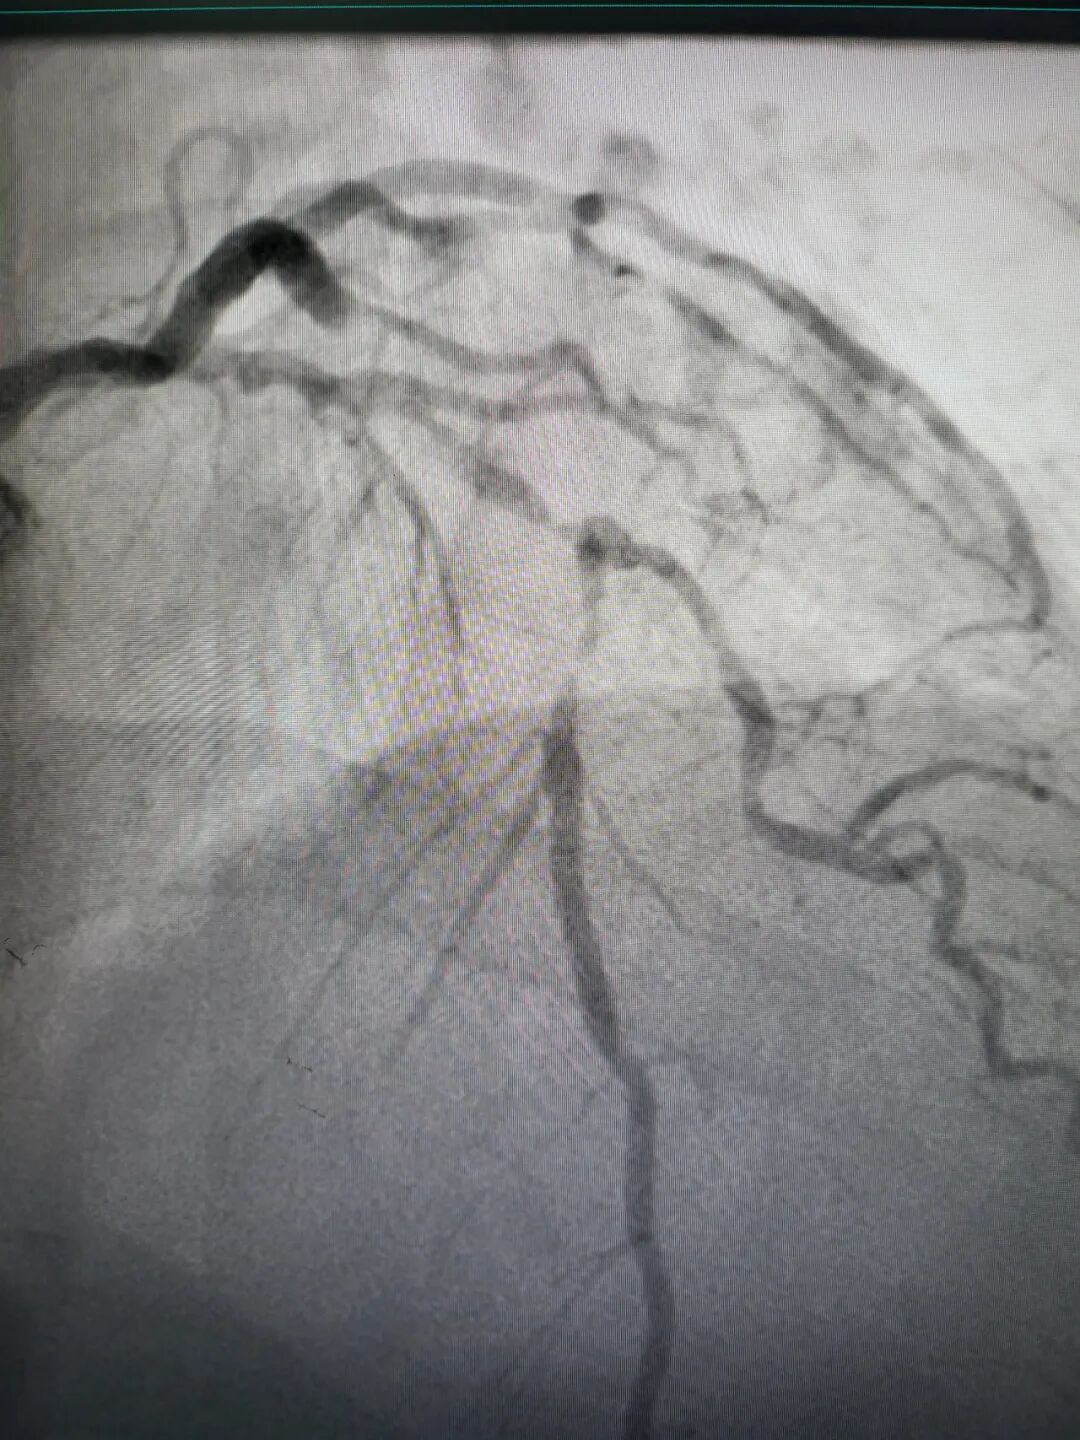

节日里,生活规律容易被打破,情绪波动也可能加剧,这些都为心血管疾病,尤其是冠心病的急性发作埋下了隐患。今年的节日,心内一接诊的患者病情尤为复杂:从正值壮年的急性心梗,到高龄且合并多种基础病的危重患者;病变类型涵盖了严重钙化的“硬骨头”、被称为冠脉介入“最后堡垒”的慢性完全闭塞病变(CTO)、严重扭曲的复杂血管、随时可能引发险情的高负荷血栓、处理难度极高的分叉病变,以及最为凶险的左主干病变。

右冠近段狭窄99%

左前降支近段狭窄99%

右冠近段次全闭塞

左前降支近中段弥漫性严重狭窄